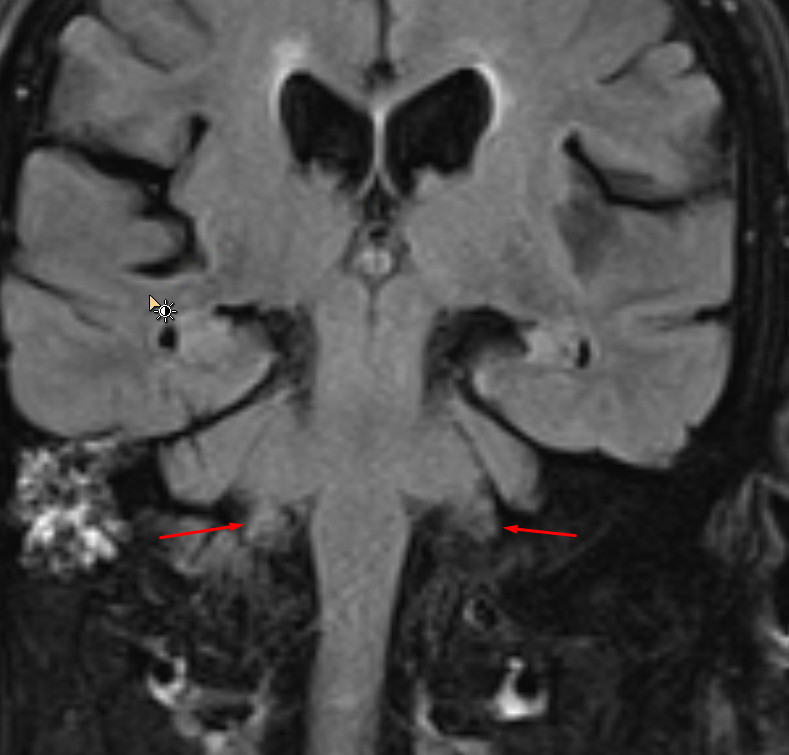

Age: 50

Sex: Female

Indication: Headache